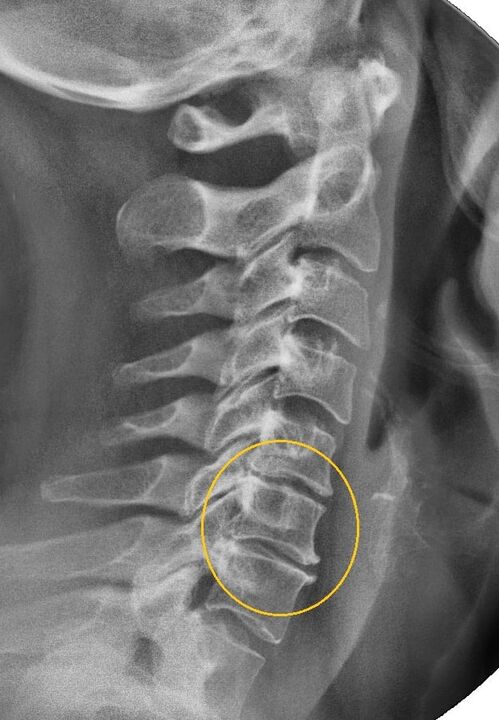

The most informative diagnostic procedure is x-ray.1st degree pathologies correspond to the 1st or 2nd radiological stage.The images obtained visualize the typical signs of the disease.

| Radiological stages of cervical osteochondrosis of the 1st degree | Characteristic signs |

|---|---|

| Step 1 | Minor changes in spinal curvature in the cervical region, affecting one or more segments |

| Step 2 | Slight thickening of the intervertebral discs, deformation of the uncinate processes, straightening of lordosis, minor growths of bony structures |